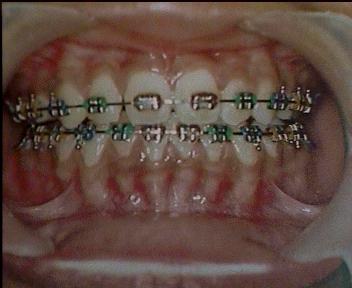

Before Treatment Intra Oral